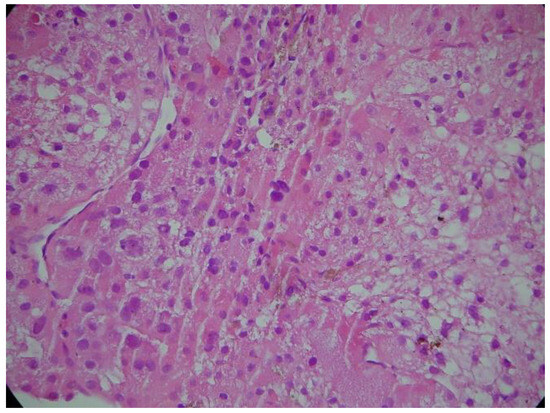

Hepatocarcinoma with Tumor Thrombus Occupying the Right Atrium and Portal Vein in a Patient with Hereditary Hemochromatosis and Liver Cirrhosis

Case report